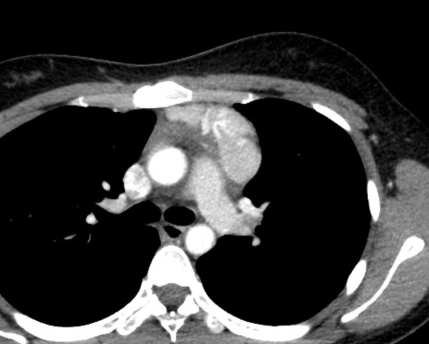

- Masse médiastinale solitaire

- Masse médiastinale solitaire ou plusieurs adénopathies hypervasculaires